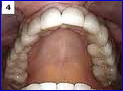

There are several types of bridges. You and your dentist will discuss the best options for your particular case. The “traditional bridge” is the most popular type and is usually made of porcelain fused to metal. Porcelain fixed bridges are most popular because they resemble your natural teeth. This type of bridge consists to two crowns that go over two anchoring teeth (abutment teeth) and are attached to pontics (artificial teeth), filling the gap created by one or more missing teeth.

We will prescribe a bridge when one or more teeth are missing and there are healthy teeth on both sides of the open space. Bridges can be made from three types of material, solid gold for reliable long wear, porcelain fused to a gold base for strength and beauty, and high-strength metal-free porcelain for optimum cosmetic results. With proper care, your new bridge will increase your overall health and instill confidence for years to come.